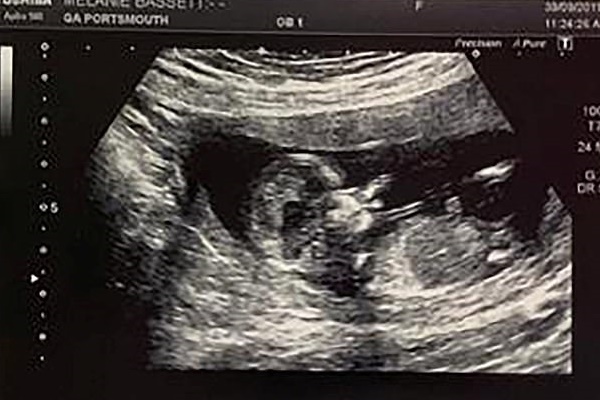

Trong một hình ảnh khác được thể hiện trên màn hình siêu âm, các bác sĩ và Samantha còn nhìn thấy được cô bé như đang giơ tay để vẫy chào mọi người.